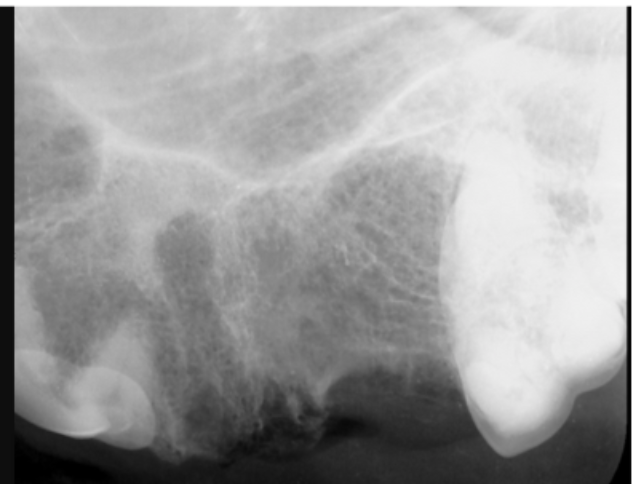

This tooth appeared fine during the oral exam.

The X-ray shows abscesses and tooth resorption, which are painful conditions. The post-operative X-ray shows complete removal of the diseased tooth. The patient healed quickly and felt much better after surgery.